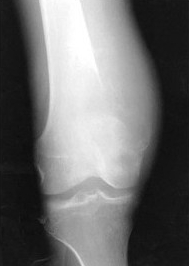

股骨下端肿瘤生产迅速,局部疼痛逐渐加重,有夜间痛,局部皮温增高,关节活动受限,X线检查有骨质破坏和骨膜反应(如图),最可能是()

A:骨瘤

B:软骨瘤

C:骨软骨瘤

D:骨肉瘤

E:骨髓瘤